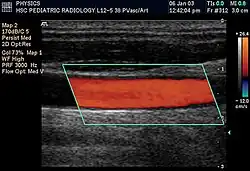

Doppler ultrasonography is medical ultrasonography that employs the Doppler effect to perform imaging of the movement of tissues and body fluids (usually blood),[1][2] and their relative velocity to the probe. By calculating the frequency shift of a particular sample volume, for example, flow in an artery or a jet of blood flow over a heart valve, its speed and direction can be determined and visualized.

Duplex ultrasonography sometimes refers to Doppler ultrasonography or spectral Doppler ultrasonography.[3] Doppler ultrasonography consists of two components: brightness mode (B-mode) showing anatomy of the organs, and Doppler mode (showing blood flow) superimposed on the B-mode. Meanwhile, spectral Doppler ultrasonography consists of three components: B-mode, Doppler mode, and spectral waveform displayed at the lower half of the image. Therefore, "duplex ultrasonography" is a misnomer for spectral Doppler ultrasonography, and more exact name should be "triplex ultrasonography".[3]

Colour Doppler shows the direction of the blood flow in red or blue (either towards or away from the transducer). Meanwhile, spectral Doppler not only shows the direction of blood flow, it also shows the phases (pulsatility) and acceleration of the blood flow. Any sudden changes in direction of blood flow produces audible sounds on the ultrasound machine.[3]

There are no standards for displaying color Doppler. Some laboratories show arteries as red and veins as blue, as medical illustrators usually show them, even though some vessels may have portions flowing toward and portions flowing away from the transducer. This results in the illogical appearance of a vessel being partly a vein and partly an artery. Other laboratories use red to indicate flow toward the transducer and blue away from the transducer. Still other laboratories display the Doppler color map in accordance with published data, with red shift representing longer wavelengths (scattered) from blood flowing away from the transducer and blue representing the shorter wavelengths from blood flowing toward the transducer. Because of this confusion and lack of standards, the sonographer must understand the underlying physics of color Doppler and the physiology of normal and abnormal blood flow in the human body (see Red shift).[4][5][6]